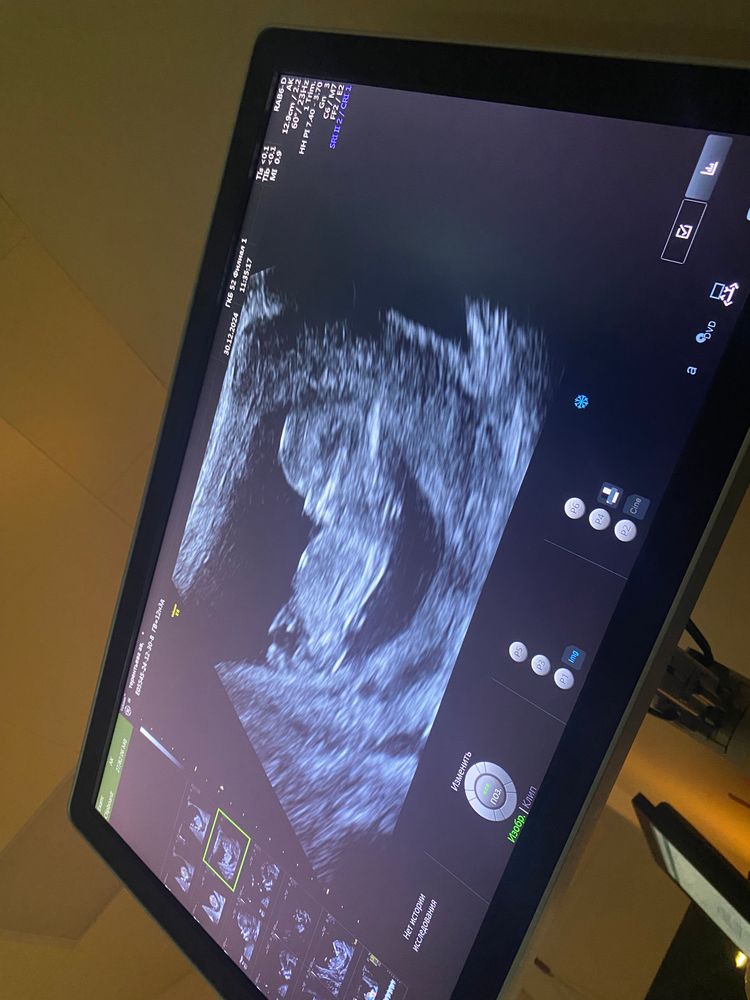

В 10 недель увидели мальчика?

bravo gun, предположили, если приблизить второе фото, то кажется, что реально оно 😁

Лина, а на скрининге что сказали ? В 10 недель нереально)

bravo gun, сказали ждать второго скрининга 😁